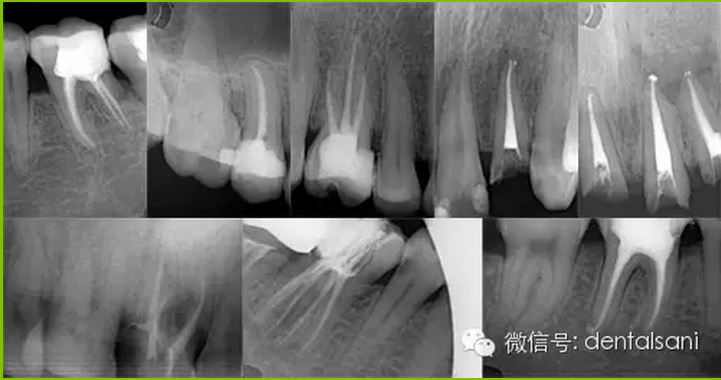

適應(yīng)癥要選擇恰當(dāng)。根據(jù)病情,牙周狀況、X線片,病人的身體狀況等各方面因素來選擇,避免治療失敗。

4. 開髓時要參照X線片,鉆針不宜進入髓腔太深,以免損傷和磨穿髓底。如果底損傷后,則難以尋找根管口,有條件者用根管口擴大器。萬一髓底磨穿,可以用丁香油氧化鋅暫封穿底處后(穿底大,應(yīng)先用雙氧水、生理鹽水輕輕沖洗),再繼續(xù)擴管。待炎癥消除后,再用磷酸鋅或銀汞合金將底充好,根管治療應(yīng)繼續(xù)進行。另外,凡是別人治療過的、開過髓的牙齒,接手之后必先拍X線片,因為有時已經(jīng)穿底。